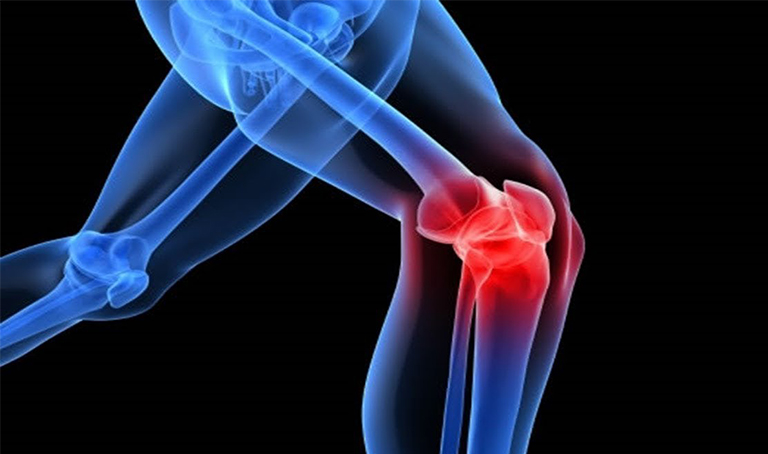

Đau khớp gối hay đau đầu gối là tình trạng xuất hiện những cơn đau ở gối và khu vực xung quanh, có thể gặp ở mọi lứa tuổi. Cơn đau thường bắt nguồn từ những vấn đề ở chính khớp gối hoặc từ các mô mềm, dây chằng, gân, túi hoạt dịch bao quanh đầu gối.

Vị trí và mức độ nghiêm trọng của cơn đau đầu gối có thể khác nhau, tùy thuộc vào nguyên nhân gây ra tình trạng này. Các triệu chứng điển hình như:

- Sưng và cứng khớp

- Khu vực bị đau đỏ và nóng ấm khi chạm vào

- Khớp yếu hoặc không ổn định

- Nghe tiếng lách tách hoặc lạo xạo ở khớp

- Không thể duỗi thẳng hoặc uốn cong đầu gối hoàn toàn